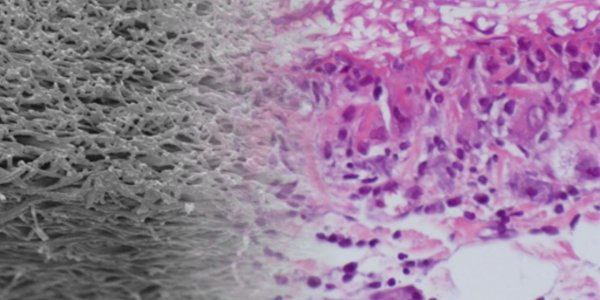

Endogenous Material For Artificial Blood Vessels

Blocked blood vessels can quickly become dangerous so it's often necessary to replace them, either by another vessel taken from the body or with artificial vascular prostheses. A new project has…